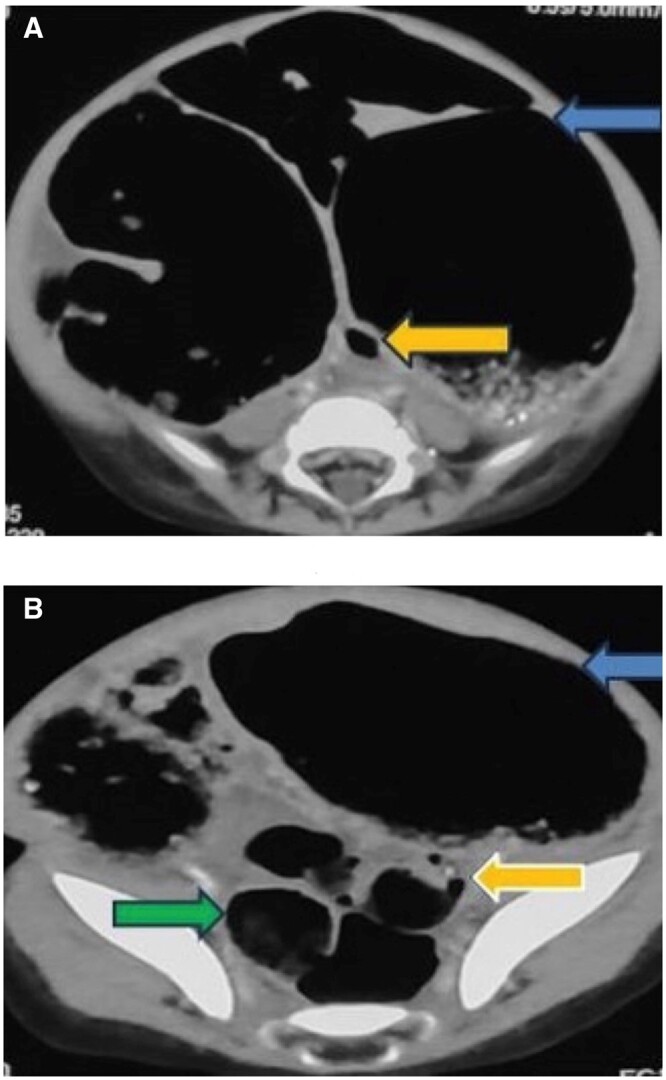

先天性乙状结肠狭窄是一种罕见的疾病,可与赫氏病相似。先天性结肠狭窄通常在出生后几周内出现。我们的病例在 2 岁时出现远端肠梗阻,并伴有慢性便秘、出生后一周内腹部逐渐胀大以及最近一周内胆汁性呕吐的病史。临床诊断为赫氏病。对比增强腹部 CT 显示肠梗阻,过渡点位于乙状结肠近端。乙状结肠近端有一短段狭窄。造影剂灌肠显示乙状结肠近端狭窄。狭窄远端肠道口径正常。手术中也发现了类似的情况。狭窄肠段存在中结肠。切除的狭窄部分在组织病理学中显示有足够的神经节细胞。

Congenital sigmoid colon stenosis is a rare entity that can mimic Hirschsprung disease. Presentation of congenital colon stenosis is usually within first few weeks of life. Our case presented with features of distal bowel obstruction at 2 years of age with the history of chronic constipation and progressive abdominal distention from first week of life and bilious vomiting for the last 1 week. Clinical diagnosis of Hirschsprung disease was made. Contrast enhanced CT abdomen showed bowel obstruction with transition point at the level of proximal sigmoid colon. There was a short segment stenosis at the level of proximal sigmoid colon. Contrast enema showed stenosis at proximal sigmoid colon. The bowel distal to stenosis was normal in calibre. Similar findings were seen during surgery. Mesocolon was present in stenosed segment of the bowel. The resected stenotic segment showed adequate ganglion cells in histopathology.